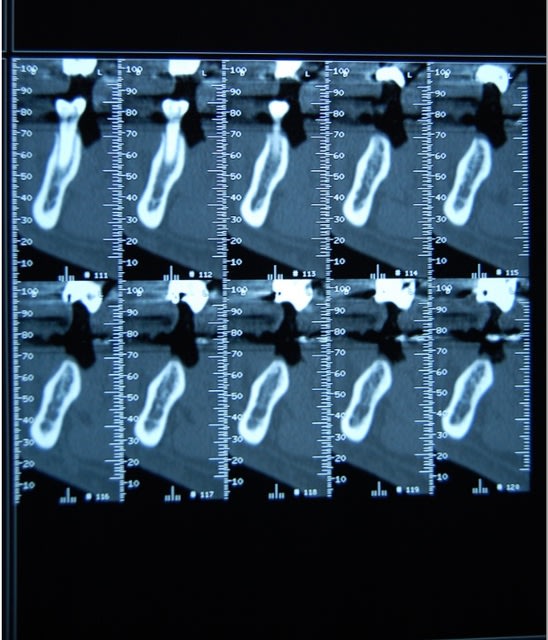

salut ,bien sur deja avec le foret pilote c'etait assez costaud avec des foret neufs(je vais poster le scan)donc dés le debut on allait passer le very hard bone sur toute la longueur ,on a fait ça pour les deux implants avec bonne irrigation .

Salut,l'implant était légèrement supracrestal(une spire) l'edentement avait 15 ans voici le scan.

vu comme c'est parti , (-4mm) je te conseille de l'enlever. et de reposer a 2mois un peut plus parallèle a la prémolaire